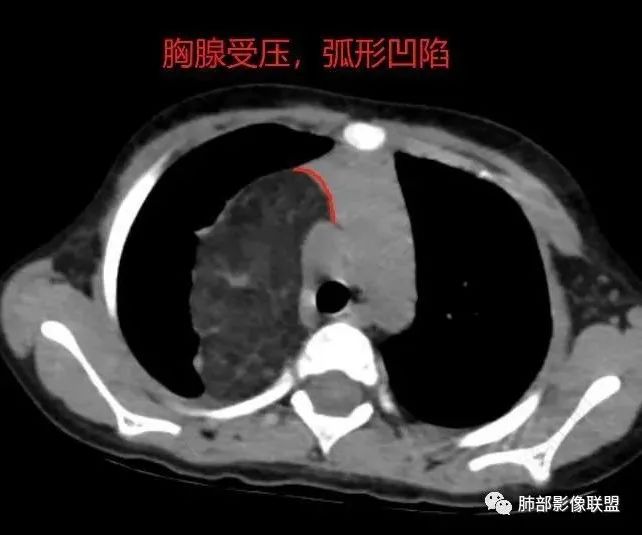

病灶属于交界区,主体位于肺内,占位效应明显,前方突入胸壁,胸腺受压变形,胸膜显示欠清楚;病灶包绕上叶肺动脉;似乎有体动脉供血。符合肺内的点:包绕上叶肺动脉分支;符合纵隔的点:前方似乎突入胸壁,与胸腺关系比较密切,但是与上腔静脉的关系提示病灶不支持纵隔来源,前纵隔的常规会将上腔静脉受压后移、外移,这是不符合的。

1.右上肺-纵隔交界区巨块影,主体位于右肺一侧,紧贴胸腺、头臂干、右锁骨下动脉、上腔静脉、奇静脉等,不能分离,但病灶整体边界清楚。注意上述相邻腔静脉等结构未见受压变形,纵隔亦未见明显向左推移,至少提示两点:

1)病灶相当柔软。

2)位于纵隔内或纵隔胸膜的可能性较小,因为受纵隔胸膜反作用力影响不明显。